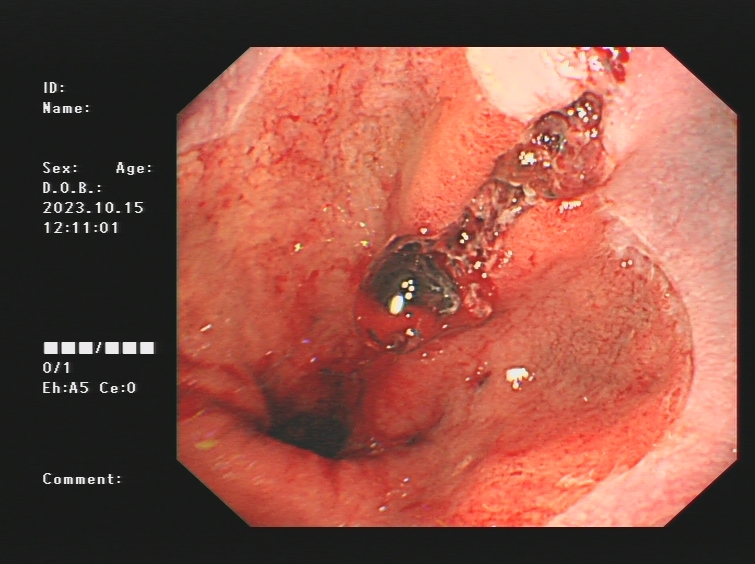

1.上消化道出血常见原因:消化性溃疡(胃溃疡、十二指肠溃疡)、食管炎、急性糜烂出血性胃炎、上消化道肿瘤(食管癌、胃癌)、剧烈呕吐造成的食管贲门黏膜撕裂伤、肝硬化引起的食管胃底静脉曲张。以下是一些常见的上消化道出血内镜图片:

食管癌、胃癌出血